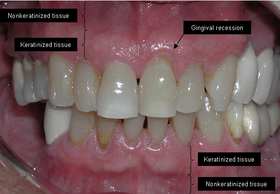

The soft tissue in the oral cavity is classified as either keratinized or nonkeratinized based on the presence of keratin in the epithelium. In health, the soft tissue immediately around the teeth is keratinized and is referred to as keratinized tissue or gingiva. Alveolar mucosa is non keratinized oral epithelium and is located apical to the keratinized tissue, delineated by the mucogingival junction (MGJ). It should also be pointed out that mucosa can surround a tooth in health. (Dorfman and Kennedy et al.) Nonkeratinized tissue also lines the cheeks (buccal mucosa), underside of the tongue and floor of the mouth. The lips contain both non-keratinized tissue (on the inside) and keratinized tissue on the outside, demarcated by the vermillion border. The dorsum of the tongue is keratinized and features many papillae, some of which contain taste buds.

Exposure of the tooth root due to loss of keratinized tissue around the neck of a tooth is referred to as gingival recession. This can result in sensitivity or pain from the exposed tooth root surface (dentin is more permeable and soft compared to enamel and DENTIN is what makes up the tooth root). Recession may also cause there to be an unasthetic appearance especially if located in the anterior dentition (front teeth). While not all cases of gingival recession REQUIRE surgical correction, there are various options if that is what the patient desires. It should be reinforced that recession left untreated will not result in tooth loss, contrary to popular belief. Also, recession that is left untreated can be maintained and the inflammation kept at bay with proper brushing and oral hygiene technique (Kennedy and Dorfman et al.) On the other hand, if one desires to pursue corrective therapy, there are a wide variety of techniques ranging from autograft (your own tissue, usually taken from the palate), allograft (someone else's tissue, cadaver), xenograft (animal, usually porcine or bovine) or simply repositioning of the tissue native to the site. The benefits of corrective therapy often result in decreased sensitivity through coverage of the root surface in addition to a gain in the keratinized tissue mentioned beforehand.